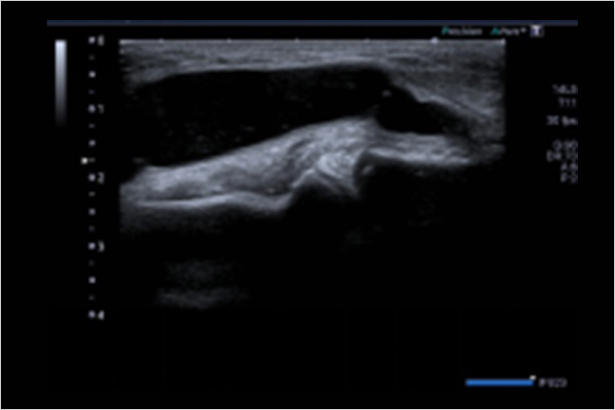

全方位的具有原始數據功能的彈性解決方案幫助您定位并評估淺表占位,準確性高,敏感度高,效率高,適用于不同臨床應用。在圖像中彩色編碼組織彈性的不同程度,使可疑組織可視化